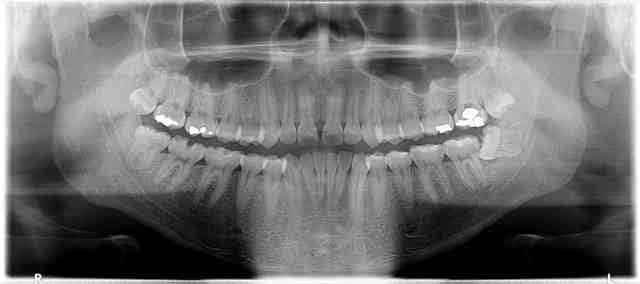

Quelques pano réalisées avec Kodak 9000 3D que j'ai en stock

Edit : je sais pas pourquoi elles sont pixelisées à mort sur Nonol...

P12 xdln3r - Eugenol

Oui j'ai eu des images comme la 0123 (la première radio). Les autres sont très pixellisées en effet.

Merci pour tes images. Je trouve la qualité pas mal du tout.

merci pour les images, mais moi je trouve la qualité très médiocre